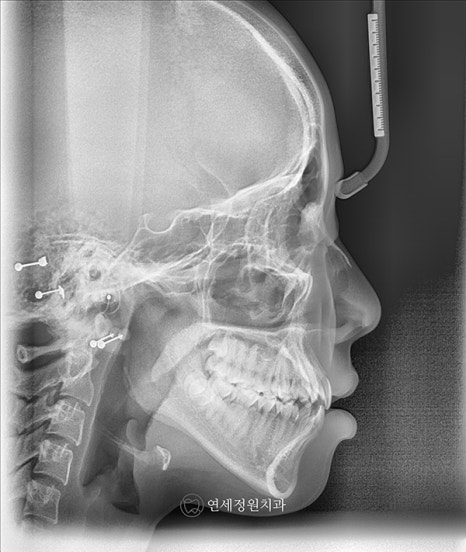

2019년 내원하였을 때 이미 유치는 다 빠지고 영구치가 다 올라온 상태였으며, 측면 엑스레이 상에서 전치부 교합은 좀더 안정적으로 잘 유지되고 있었습니다. 이제 영구치가 다 올라와서 2차교정을 시작해도 되는 시기였으나, 환자가 6개월 뒤 캐나다로 유학을 갈 예정이어서 교정 시작 시기는 환자분 스케줄에 맞춰서 시작하셔도 된다고 설명을 드렸습니다.

2019년 7월